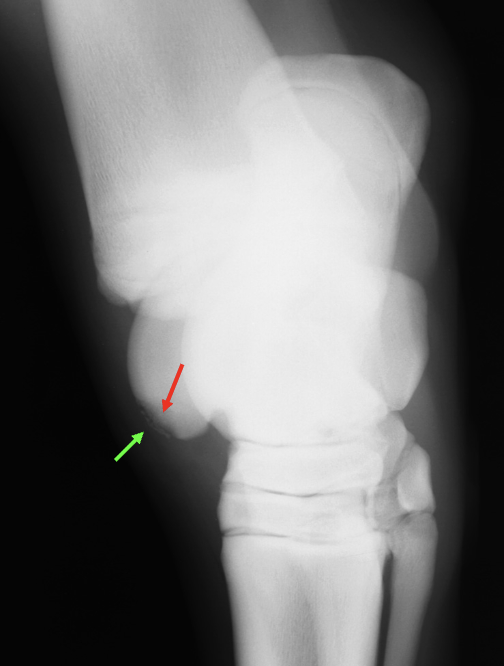

What is shown in these images?

A

tarsal bone collapse; early stage